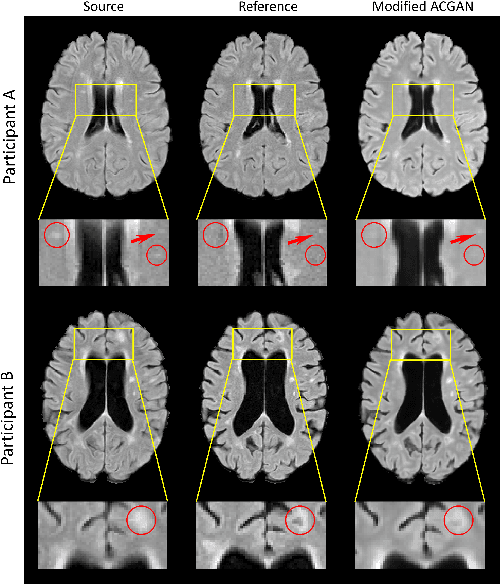

Abstract:Multiple Sclerosis (MS) is a chronic progressive neurological disease characterized by the development of lesions in the white matter of the brain. T2-fluid-attenuated inversion recovery (FLAIR) brain magnetic resonance imaging (MRI) provides superior visualization and characterization of MS lesions, relative to other MRI modalities. Longitudinal brain FLAIR MRI in MS, involving repetitively imaging a patient over time, provides helpful information for clinicians towards monitoring disease progression. Predicting future whole brain MRI examinations with variable time lag has only been attempted in limited applications, such as healthy aging and structural degeneration in Alzheimer's Disease. In this article, we present novel modifications to deep learning architectures for MS FLAIR image synthesis, in order to support prediction of longitudinal images in a flexible continuous way. This is achieved with learned transposed convolutions, which support modelling time as a spatially distributed array with variable temporal properties at different spatial locations. Thus, this approach can theoretically model spatially-specific time-dependent brain development, supporting the modelling of more rapid growth at appropriate physical locations, such as the site of an MS brain lesion. This approach also supports the clinician user to define how far into the future a predicted examination should target. Accurate prediction of future rounds of imaging can inform clinicians of potentially poor patient outcomes, which may be able to contribute to earlier treatment and better prognoses. Four distinct deep learning architectures have been developed. The ISBI2015 longitudinal MS dataset was used to validate and compare our proposed approaches. Results demonstrate that a modified ACGAN achieves the best performance and reduces variability in model accuracy.